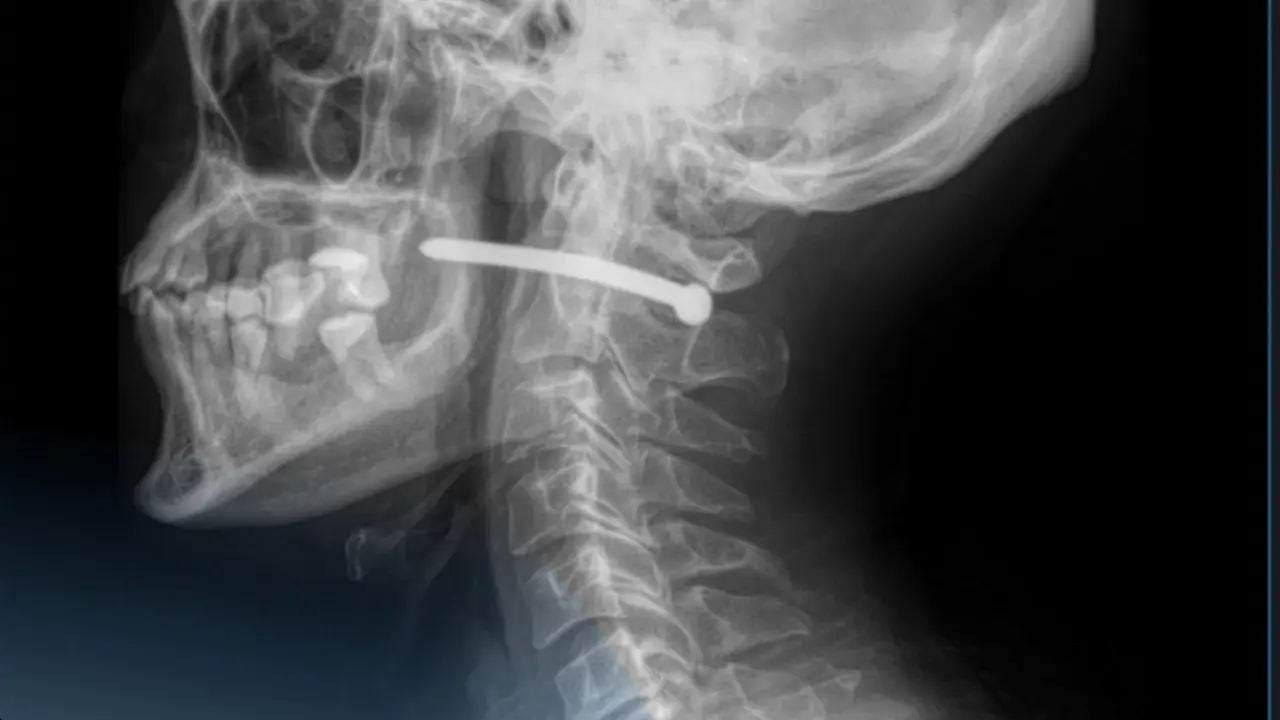

Пациенту сделали рентген и увидели, что гвоздь прошёл рядом с шейным отделом позвоночника.

"Мужчине чудом повезло – жизненно важные структуры не были задеты. Челюстно-лицевые хирурги провели удаление инородного тела, ревизию и обработку раны", – сообщили в больнице.